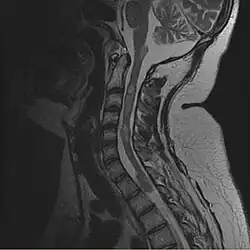

- Rückenmark: Ebenso häufig finden sich spinale (das Rückenmark betreffende) Raumforderungen (in der Medizin bezeichnet der Begriff Raumforderung in vielen Fällen eine Gewebswucherung). Bei den Patienten mit einer NF Typ II werden die cranialen (den Schädel betreffenden) Raumforderungen fast immer symptomatisch (z.Bsp. Hörminderung). Die spinalen Raumforderungen werden aber nur in ca. 40 % der Fälle symptomatisch. Die spinalen Tumoren werden in zwei Gruppen unterteilt. Einmal findet man intramedulläre Raumforderungen. Damit sind Tumoren gemeint, die sich in der Gewebssubstanz des Rückenmarkes finden. Hier findet man vor allem Astrozytome und Ependymome. Zum anderen finden sich extramedulläre Raumforderungen. Hiermit meint man Tumoren oder Gewebsveränderungen, die sich im Rückenmarkskanal, aber außerhalb der Rückenmarkssubstanz befinden. Der extramedulläre Raum ist der Spalt zwischen der Oberfläche der Rückenmarkssäule und der knöchernen Wand des Rückenmarkskanales innerhalb der Wirbelsäule. In diesen Fällen treten vornehmlich Schwannome und Meningeome auf.

- V. F. Mautner u. a.: Spinal tumors in patients with neurofibromatosis type 2: MR imaging study of frequency, multiplicity, and variety. In: AJR Am J Roentgenol. 1995 Oct; 165(4), S. 951–955. Erratum in: AJR Am J Roentgenol., Mai 1996, 166(5), S. 1231. PMID 7676998